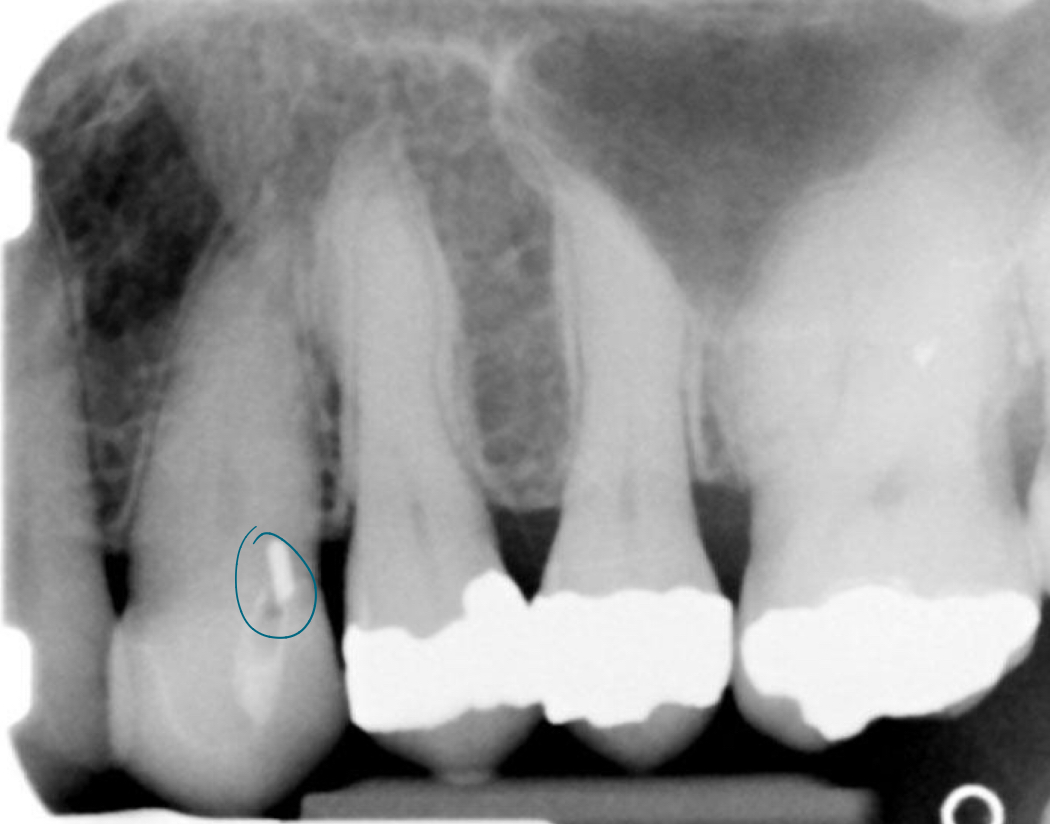

Unloaded implant

Implant loaded